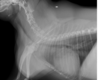

What can be seen?

tracheal collapse

tracheal hypoplasia

none of them

both of them

Tracheal collapse